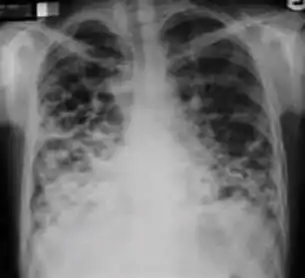

7. Other - Any other finding suggestive of active TB, such as miliary TB. Miliary findings are nodules of millet size (1 to 2 millimeters) distributed throughout the parenchyma.

Chest X-ray findings that can suggest inactive TB